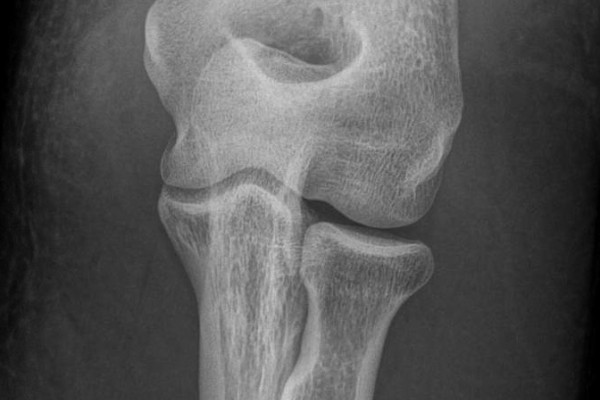

El codo de golfista o epitrocleitis

El llamado codo de golfista, epicondilitis medial o epitrocleitis, es una patología similar al codo de tenista o epicondilitis lateral. Las principales diferencias son la localización del dolor, (que en el codo del golfista se localiza en la parte interna del codo) y la actividad que provoca esta patología. Sin embargo, las dos son provocadas habitualmente por sobreuso de los mmica del nervio cubital en el codo, puede provocar dolor lancinante y disestesias o alteraciones de la sensibilidad de los úsculos del antebrazo, que acaban provocando dolor en el codo y limitación de la función.

Se trata de una tendinitis de la musculatura del antebrazo que se inserta en la parte interna del codo. Esta musculatura es la responsable de los movimientos de flexión de la muñeca y de pronación (movimiento que coloca en antebrazo con la palma de la mano hacia abajo). A veces, y debido a la cercanía anatómica del nervio cubital en el codo, se puede asociar a síntomas de compresión de este nervio, provocando dolor lancinante y disestesias o alteraciones de la sensibilidad de los dedos (anular y meñique), especialmente cuando se coge un objeto con la mano.